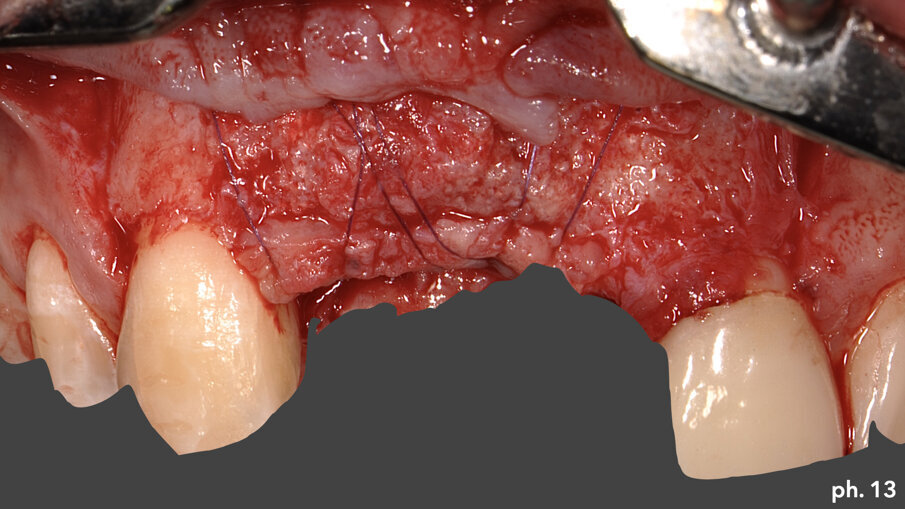

Dopo aver rimosso le viti di fissazione, la griglia stessa viene tagliata e separata in due porzionilungo la linea predefinita in senso longitudinale. Le stesse vengono poi rimosse delicatamente avvalendosi dell’aiuto di uno scollaperiostio e di un bisturi (Fig. 11). A questo punto una volta denudato il piano osso e valutata la sua qualità e quantità, possiamo passare all’inserimento degli impianti che in questo caso è stato effettuato in tecnica classica, senza l’ausilio di una mascherina per un inserimento computer guidato. Gli impianti scelti nella risoluzione di questa situazione sono due impianti Straumann BLT 4,1 x 10 mm (Fig. 12). Una volta inseriti gli impianti si è provveduto ad effettuare un assottigliamento del lembo palatino5; per permettere al paziente una miglior detersione dei presidi implanto-protesici, oltre che per consentirci l’utilizzo della porzione epitelio connettivale rimossa per ispessire coronalmente il tessuto gengivale nella zona di inserimento degli impianti. Eliminata chirurgicamente la porzione epiteliale del prelievo, abbiamo stabilizzato quella connettivale a livello osseo crestale utilizzando una sutura riassorbibile che ancorasse il tessuto al periostio (Fig. 13). L’aumento in senso verticale del tessuto cheratinizzato è evidenziato dall’immagine numero 14 dove possiamo valutare il livello coronale del tessuto molle prima della rigenerazione, la linea bianca, al momento della rimozione della griglia, la linea arancione, e infine alla maturazione dell’innesto di tessuto connettivo, la linea di colore verde (Fig. 14). Una volta maturati i tessuti molli sono stati quindi inseriti quattro elementi provvisori singoli, dall’elemento 1.2 all’elemento 2.2, di cui due su impianti e due su denti; le modifiche nel tempo di questi provvisori secondo la tecnica della compressione dinamica, ci hanno permesso di condizionare la guarigione degli stessi tessuti molli6 prima di passare alla fase di protesizzazione definitiva. I manufatti protesici definitivi sono quattro corone singole in zirconio-ceramica su impianti e su elementi naturali: in particolare le corone su 1.1 e 1.2 sono avvitate agli impianti (Fig. 15).